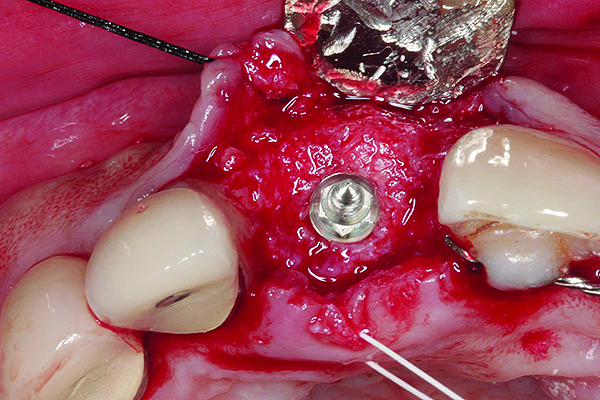

In cases with an incomplete facial plate, the ice cone technique was recommended.20 In this method, a collagen membrane was trimmed to the shape of an ice cone and placed into the socket against the inner aspect of the facial bone. The socket was filled with bone substitutes, and the coronal portion of the membrane was used to cover and protect the underlying bone substitutes. A non-resorbable PTFE membrane can be used for site preservation as well.21 This membrane, if secured to bone, can be left exposed, and epithelialization will occur over it. It was found that sockets grafted with a mineralized bone allograft and PTFE membrane had 47.4% new bone formation and 14.7% residual graft particles. In addition, there was minimum resorption of the buccal bone thickness, as indicated by a 0.3-mm horizontal bone resorption and a 0.25-mm vertical bone resorption.22 A recent systematic review reported that the use of PTFE membranes in ridge preservation shows potential in maintaining ridge dimensions23 and possibly aiding in increasing the zone of keratinized mucosa. Therefore, the use of PTFE membrane may be preferred in ridge preservation of sites in the esthetic zone. Figure 1 and Figure 2 illustrate the use of PTFE membrane in ridge preservation for implant replacement in the esthetic zone. Other authors have also attempted primary closure of the socket or to improve the ridge topography with soft-tissue grafts, but it has not been proven to be effective in increasing bone regeneration.18

Placement of implant. Notice the bucco-palatal bone thickness gained from the ridge preservation technique.

Figure 2